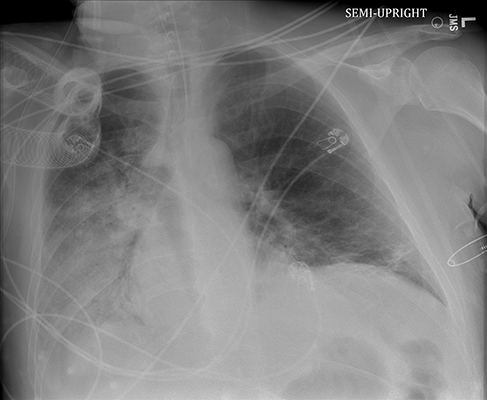

Chest X-ray

There is an alveolar pattern of opacification in the right middle and lower lobes. The former is apparent due to some obscuration of the right cardiac border, while the latter is apparent due to obscuration of the right hemidiaphragmatic border. There's probably some plate atelectasis in the left lower lobe. Cardiac contours appear normal. We can't see the right costophrenic angle, so there could be some fluid there. No apparent pneumothorax. The ETT appears in good position (not measured here, but in the correct range above the carina). In considering the overall lung volumes present bilaterally, but especially the right, we are right to be concerned that this RML/RLL opacification represents consolidation not from atelectasis.

Should we start antibiotics? True, this opacification could represent pneumonia. However, the patient is not hypoxemic, secretion burden hasn't been commented on, and there hasn't been a fever or leukocytosis. At this stage, the patient has a radiographic finding and perhaps could've had a pneumonitis. There isn't any clinical evidence pointing towards a pneumonia.